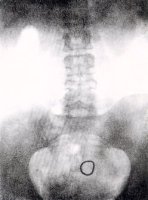

由左及右:放送格拉芬伯环的器械、格拉芬伯环样品、显示放置的格拉芬伯环的X-光照片

From the

left: Top:

Device for

inserting

the

Gräfenberg-ring,

three

samples of

the ring,

X-ray

showing

position of

inserted

ring